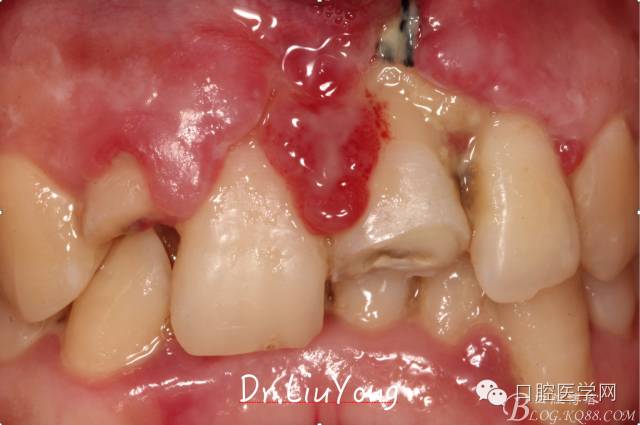

檢查:面部對稱無腫脹畸形,張口度正常,口內(nèi)檢查可見A2牙冠缺失,可見直徑約1.5mm左右穿髓孔,冷熱刺激痛+,叩痛+,探痛+,近中斷面探診位于齦下1.5mm,A1B1B2松動2-3度,B1牙冠缺失1/2,冷熱刺激痛-,叩痛+,B2牙冠完整,A2-B2牙齦紅腫,探診極易出血,全口口腔衛(wèi)生差,牙結(jié)石++,A1B1之間牙齦乳頭紅腫嚴(yán)重,B1唇側(cè)牙齦萎縮明顯,牙齦邊緣可見縫線兩處,局部有滲出,齦緣冠方1mm處見白色骨塊,松動,觸痛明顯,觸及骨塊時可見B1及B2近中唇側(cè)牙齦動度,B1B2之間唇側(cè)牙齦乳頭缺失,B2近中根面可見大量牙結(jié)石。重度深覆合,牙尖交錯位時C3-D2咬至上前牙腭側(cè)齦緣,A1切端咬至C12唇側(cè)齦緣。其余牙齒未見明顯異常。

術(shù)前口內(nèi)照片如下: